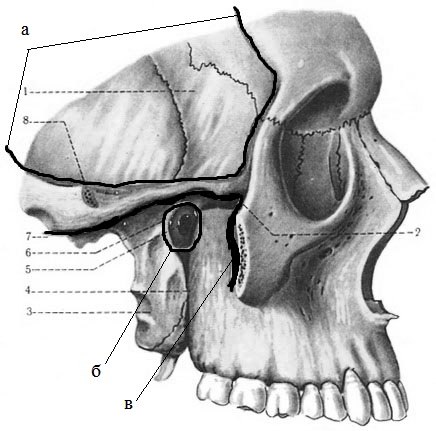

Анатомические особенности: фотографии ямок черепа, височной и подвисочной крылонебной